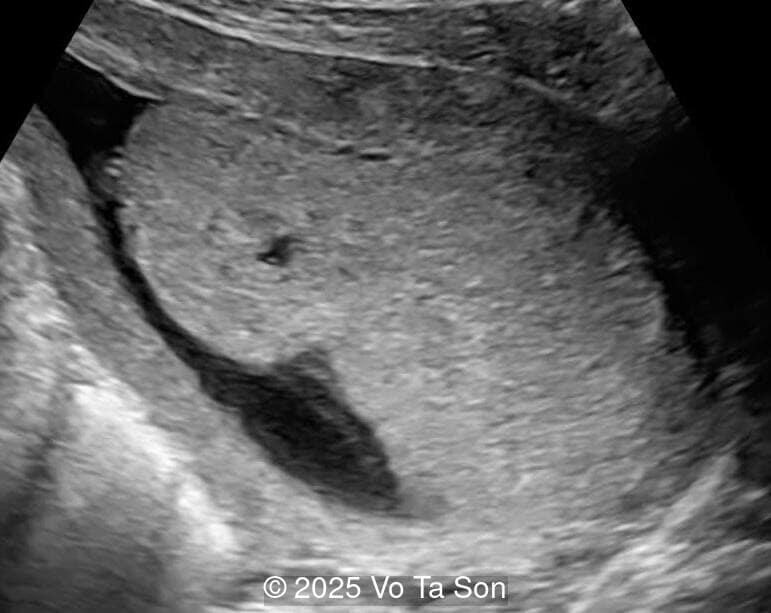

A primary spinal lesion is observed in the sacral region, characterized by a posterior vertebral arch defect and a protruding meningeal sac.

Image 1 A primary spinal lesion is observed in the sacral region, characterized by a posterior vertebral arch defect and a protruding meningeal sac.